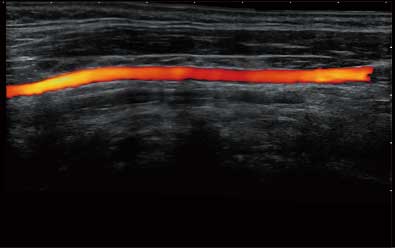

• Wi-Flow

通过对组织运动信息、血流信号及背景噪声进行准确智能的阈值判定,高效提取出微弱血流信号,获得高灵敏度和空间分辨率的血流图像,为临床提供更加真实和丰富的诊断信息。

临床图